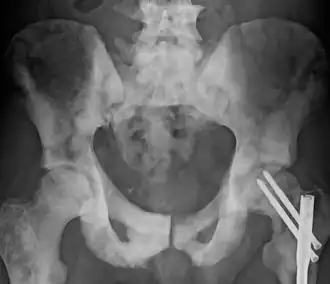

Pelvis com esclerose causada por metástase.

Osteosclerose é o aumento anormal da densidade ósseo,[1] devido à substituição de osso trabecular (saudável) por osso compacto, mais pesado, menos maleável e atrofiando a medula óssea. Pode ser detectada por uma radiografia simples por uma marcada opacidade. É um sintoma de muitas doenças diferentes, algumas hereditárias e outras adquiridas.